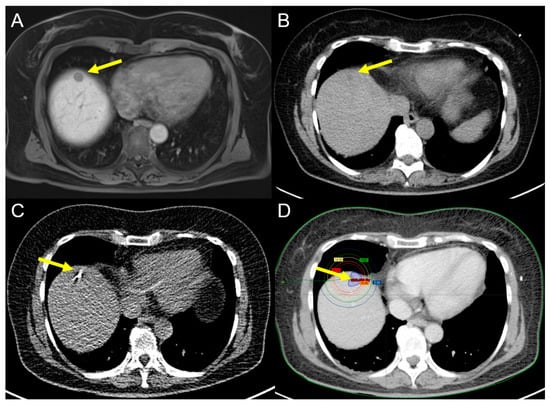

2.1.1. Radiofrequency Ablation (RFA)

2.1.2. Microwave Ablation (MWA)